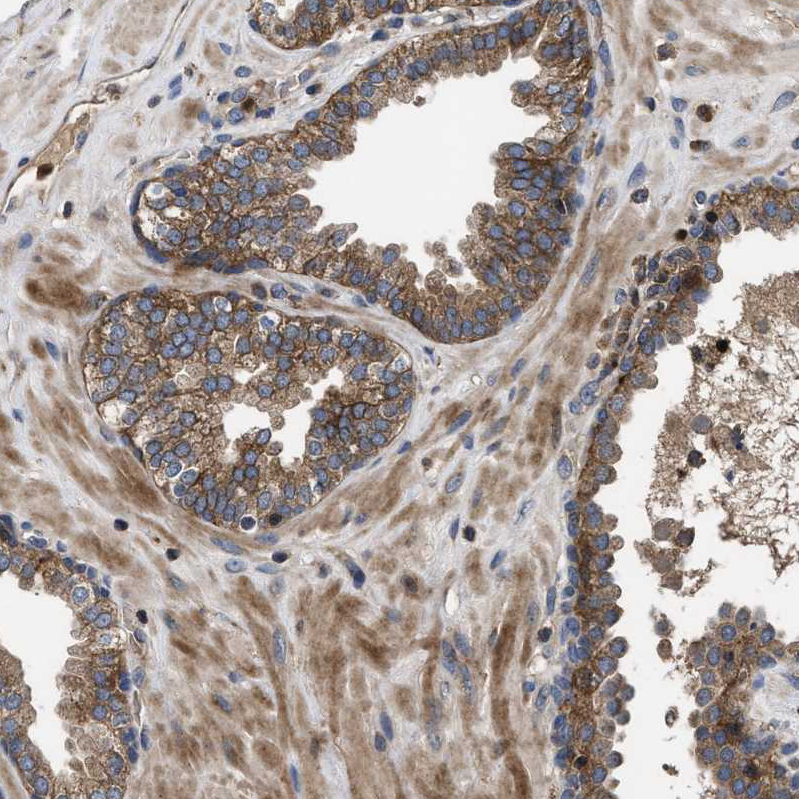

Immunohistochemical staining of human testis shows moderate to strong granular cytoplasmic positivity in seminiferous ducts.